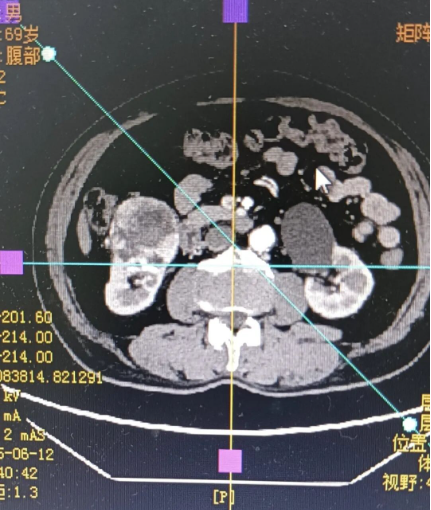

进一步的增强全腹CT检查,更是让病情显得“错综复杂”:肿瘤最大直径达6.7cm,初步怀疑是肾癌中常见的透明细胞癌,苏大爷同时还合并有肝囊肿、双肾囊肿、右肾盏小结石,左侧肾上腺可能存在增生,右侧髂内动脉起始部甚至有动脉瘤伴附壁血栓。多重基础疾病叠加,给后续治疗出了一道“难题”。